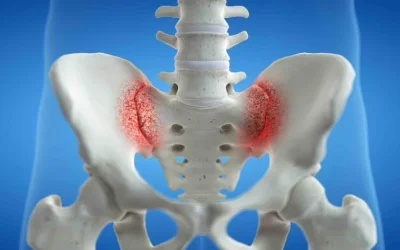

SACROILITIS o SACROILEITIS: Dolor o inflamación de la articulación sacroiliaca

La sacroilitis o sacroileitis se refiere al dolor o inflamación de la articulación sacroilíaca, que puede afectar de forma unilateral o bilateral. Es decir...